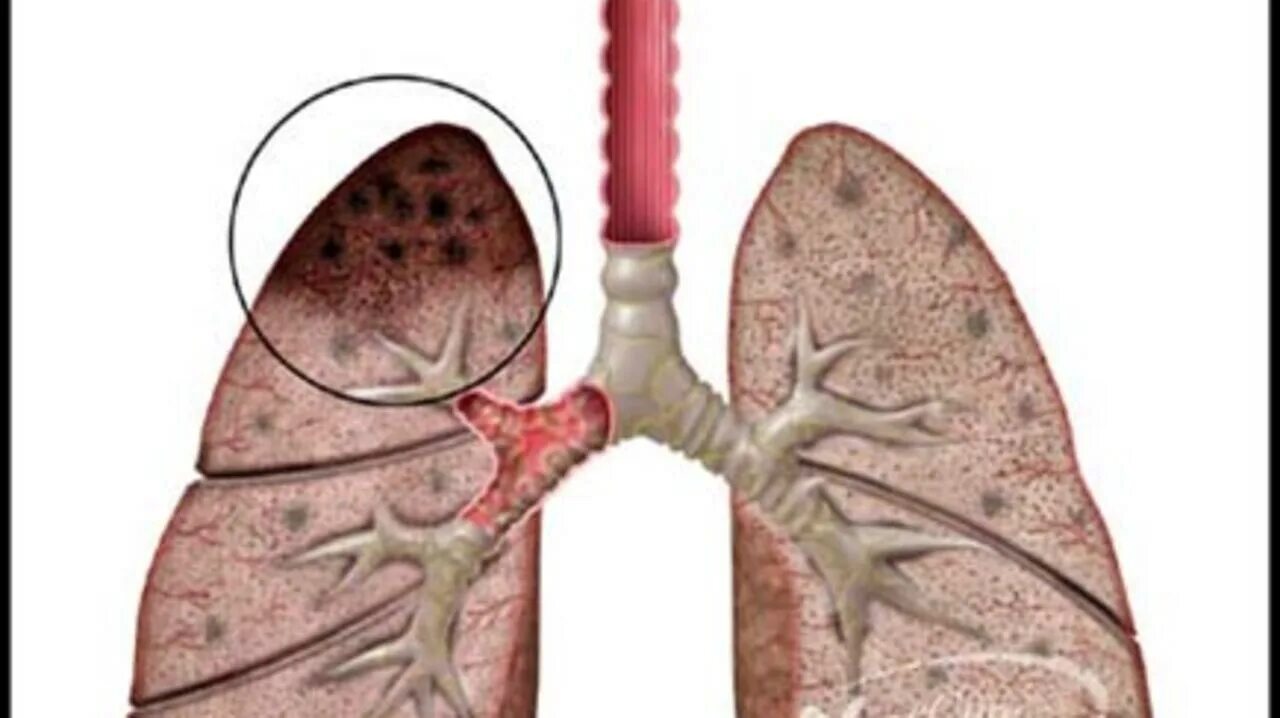

Аортокоронаросклероз легких что это такое